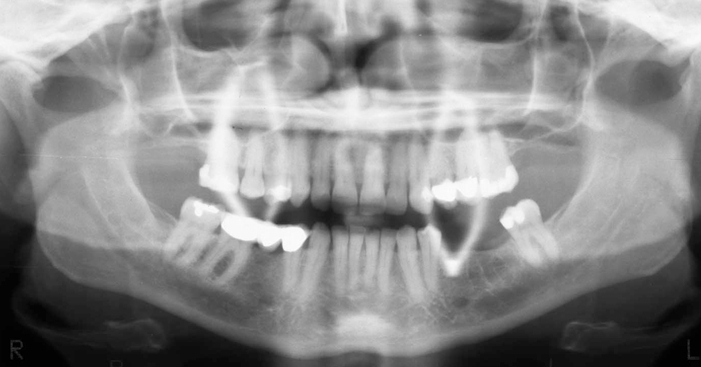

What is wrong with this image?

too far forward

double real image of cervical spine (superimposed on ramus)